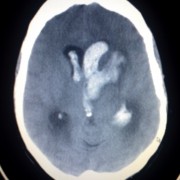

Une ischémie cérébrale transitoire ( ICT), ou un mini-AVC survient à la suite de l’interruption de la circulation sanguine dans le cerveau pendant un court laps de temps. Lire la suite